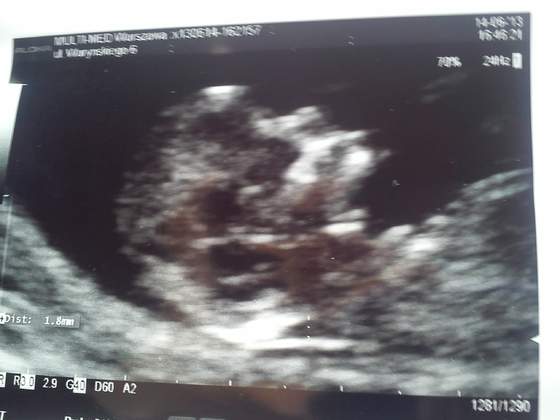

Tak jak obiecałam:

14.06.jpg

Załączniki

• 14.06.jpg

21,6 KB · Wyświetleń: 54

misia- piękna dzidzia:-)